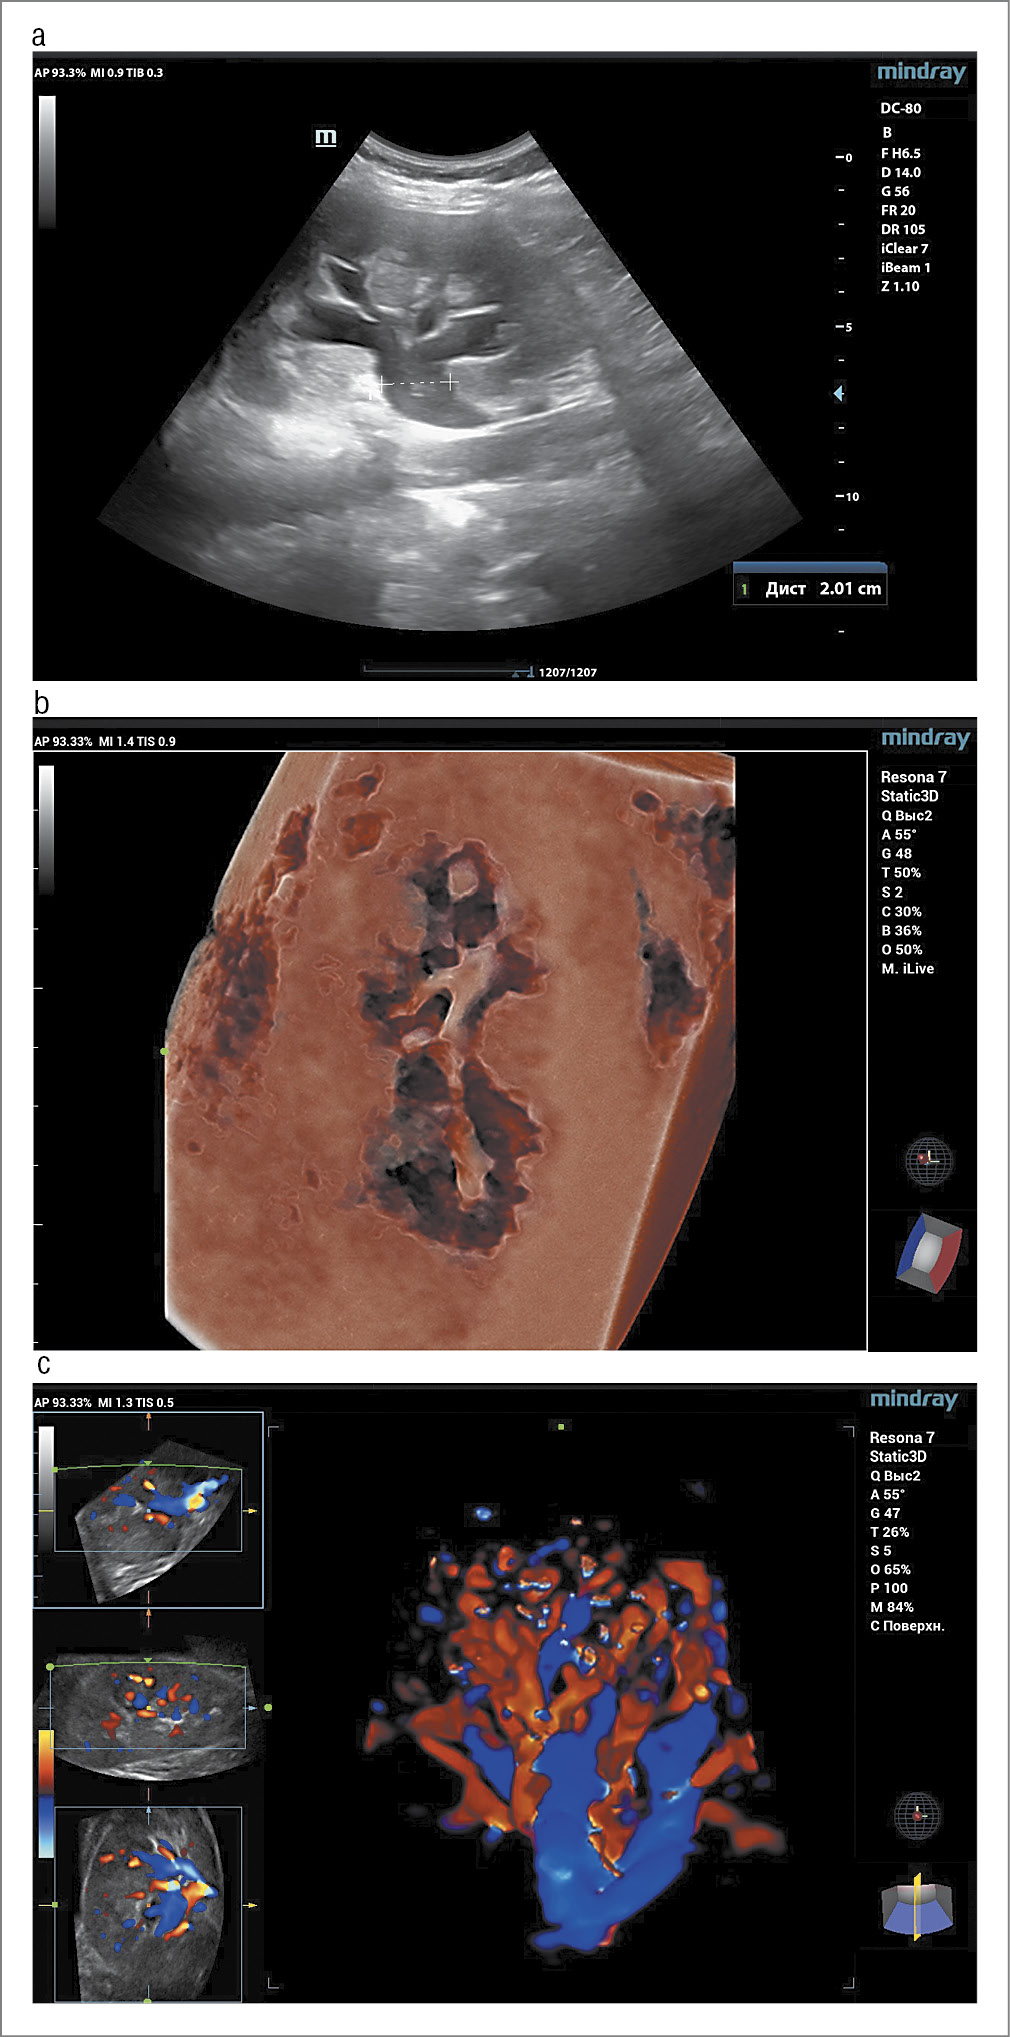

Беременная 24 лет (1-я беременность, 1-е роды) встала на учет по беременности до 12 нед. Обследована согласно приказу Минздрава России от 20.10.2020 №1130н. В I триместре обнаружен генотип ДНК ВПЧ (тип 45) – 3,7 lg/105 клеток. Цитограмма с патологией плоского эпителия ASC-US. Коэкспрессия онкобелков p16/Ki67 не обнаружена (низкая вероятность H-SIL, рекомендации по результатам ВПЧ-ПАП-теста). Данные скрининга I триместра не указывали на повышенные риски хромосомных аномалий, выявлены низкие риски развития ранней и поздней преэклампсии. Во II триместре на 18-й неделе у женщины развился острый тонзиллит с гипертермией до 39°C с очевидными проявлениями воспаления в анализах крови (общий анализ крови и С-реактивный белок). Проведен курс комплексной терапии, включая антибиотикотерапию (Амоксиклав в течение 7 дней). На 20-й неделе в общем анализе мочи выявлена бактериурия, в анализе на посев мочи – рост Escherichia coli 106 КОЕ/мл, женщина предъявляла жалобы на учащенное мочеиспускание, боли в области уретры. Проведено УЗИ почек и мочевого пузыря. На эхограммах обнаружено типичное расположение почек с обеих сторон, с нормальными общими размерами. В левой почке не отмечено патологических эхографических изменений. В правой почке (рис. 2) выявлено увеличение лоханки до 2 см и расширение чашечного комплекса до 18 мм с расширением чашечек 2-го порядка до 12 мм. Структура паренхимы правой почки, а также данные ЦДК отмечены в пределах нормы. В просвете чашек выявлены множественные гиперэхогенные участки до 4 мм в диаметре. Акустические тени позади образований не выявлены. Признаков мегауретера не отмечено. Данная картина нами интерпретирована как начальные проявления ОУ (справа) с неспецифическими эхографическими признаками воспалительного процесса. Ультразвуковая картина мочевого пузыря без особенностей (см. рис. 2).

Рис. 2. Результаты эхографии. Случай 2: a – В-сканирование. Продольное изображение почки. Начальные проявления ОУ (расширенные чашечки и лоханка); b – 3D/4D-сканирование с цифровым рендорингом. Объемное изображение лоханочного комплекса с деталями содержимого; с – 3D/4D-сканирование в режиме ЦДК. Изображение неосложненной васкуляризации паренхимы почки.

Fig. 2. Sonogram. Case 2: a – B-scan. Longitudinal image of the kidney. Initial manifestations of OU (dilated calyces and pelvis); b – 3D/4D scanning with digital rendering. Volumetric image of the pelvic complex with details of the content; c – 3D/4D scanning in CFI mode. Image of uncomplicated vascularization of the renal parenchyma.

Пациентка получила терапию фосфомицином 3 г с последующим контролем общего анализа мочи (нормальные показатели) и посева мочи (патологического роста не выявлено). Эхографическая картина плода во II и III триместре соответствовала нормативным значениям. Беременность протекала в дальнейшем без особенностей. Произошли своевременные роды – мальчик 3400 г и 52 см, с оценкой по шкале Апгар 9/9 баллов. Послеродовый период протекал без особенностей. Однако через 2 нед после родов появился дискомфорт в области поясницы. Женщине проведено эхографическое исследование почек (см. рис. 2) Почки с обеих сторон – без изменений в паренхиме. В правой почке отмечается расширение лоханки, расширение чашечек до 15 мм и гиперэхогенные включения до 6 мм без акустической тени (по-видимому, воспалительный детрит).